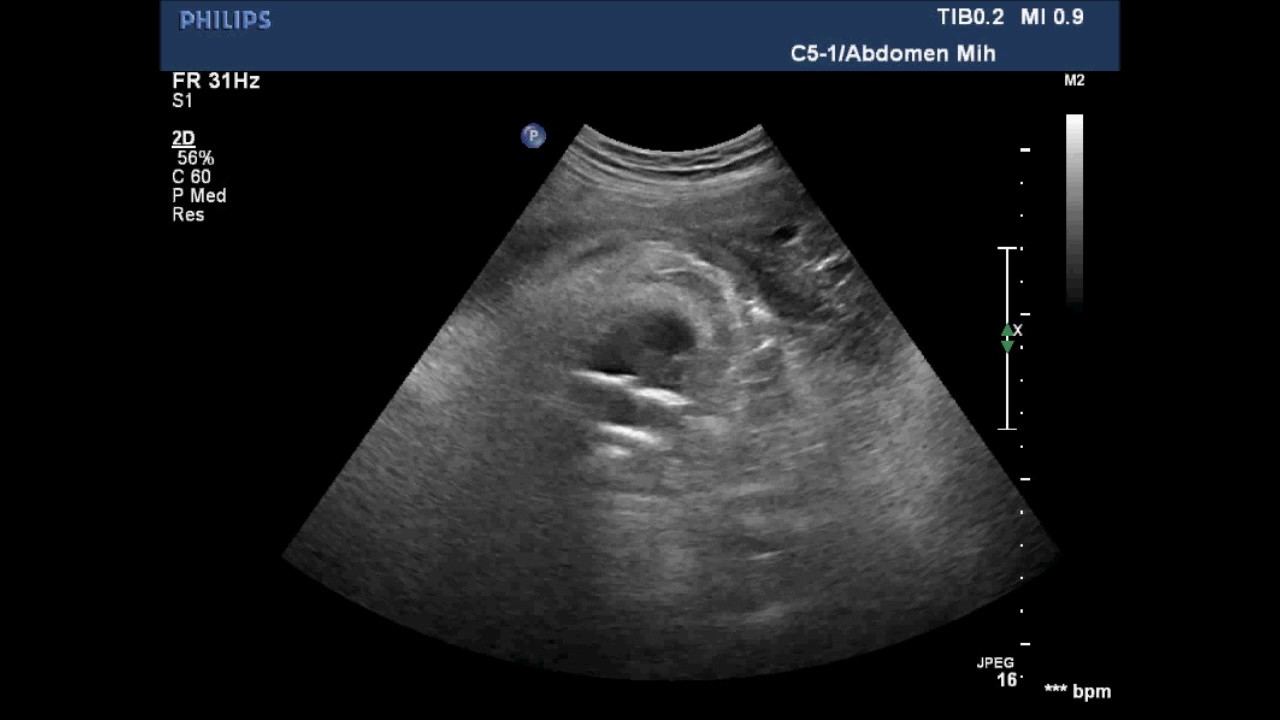

Узи видео уроки

Узи видео уроки 87 фото